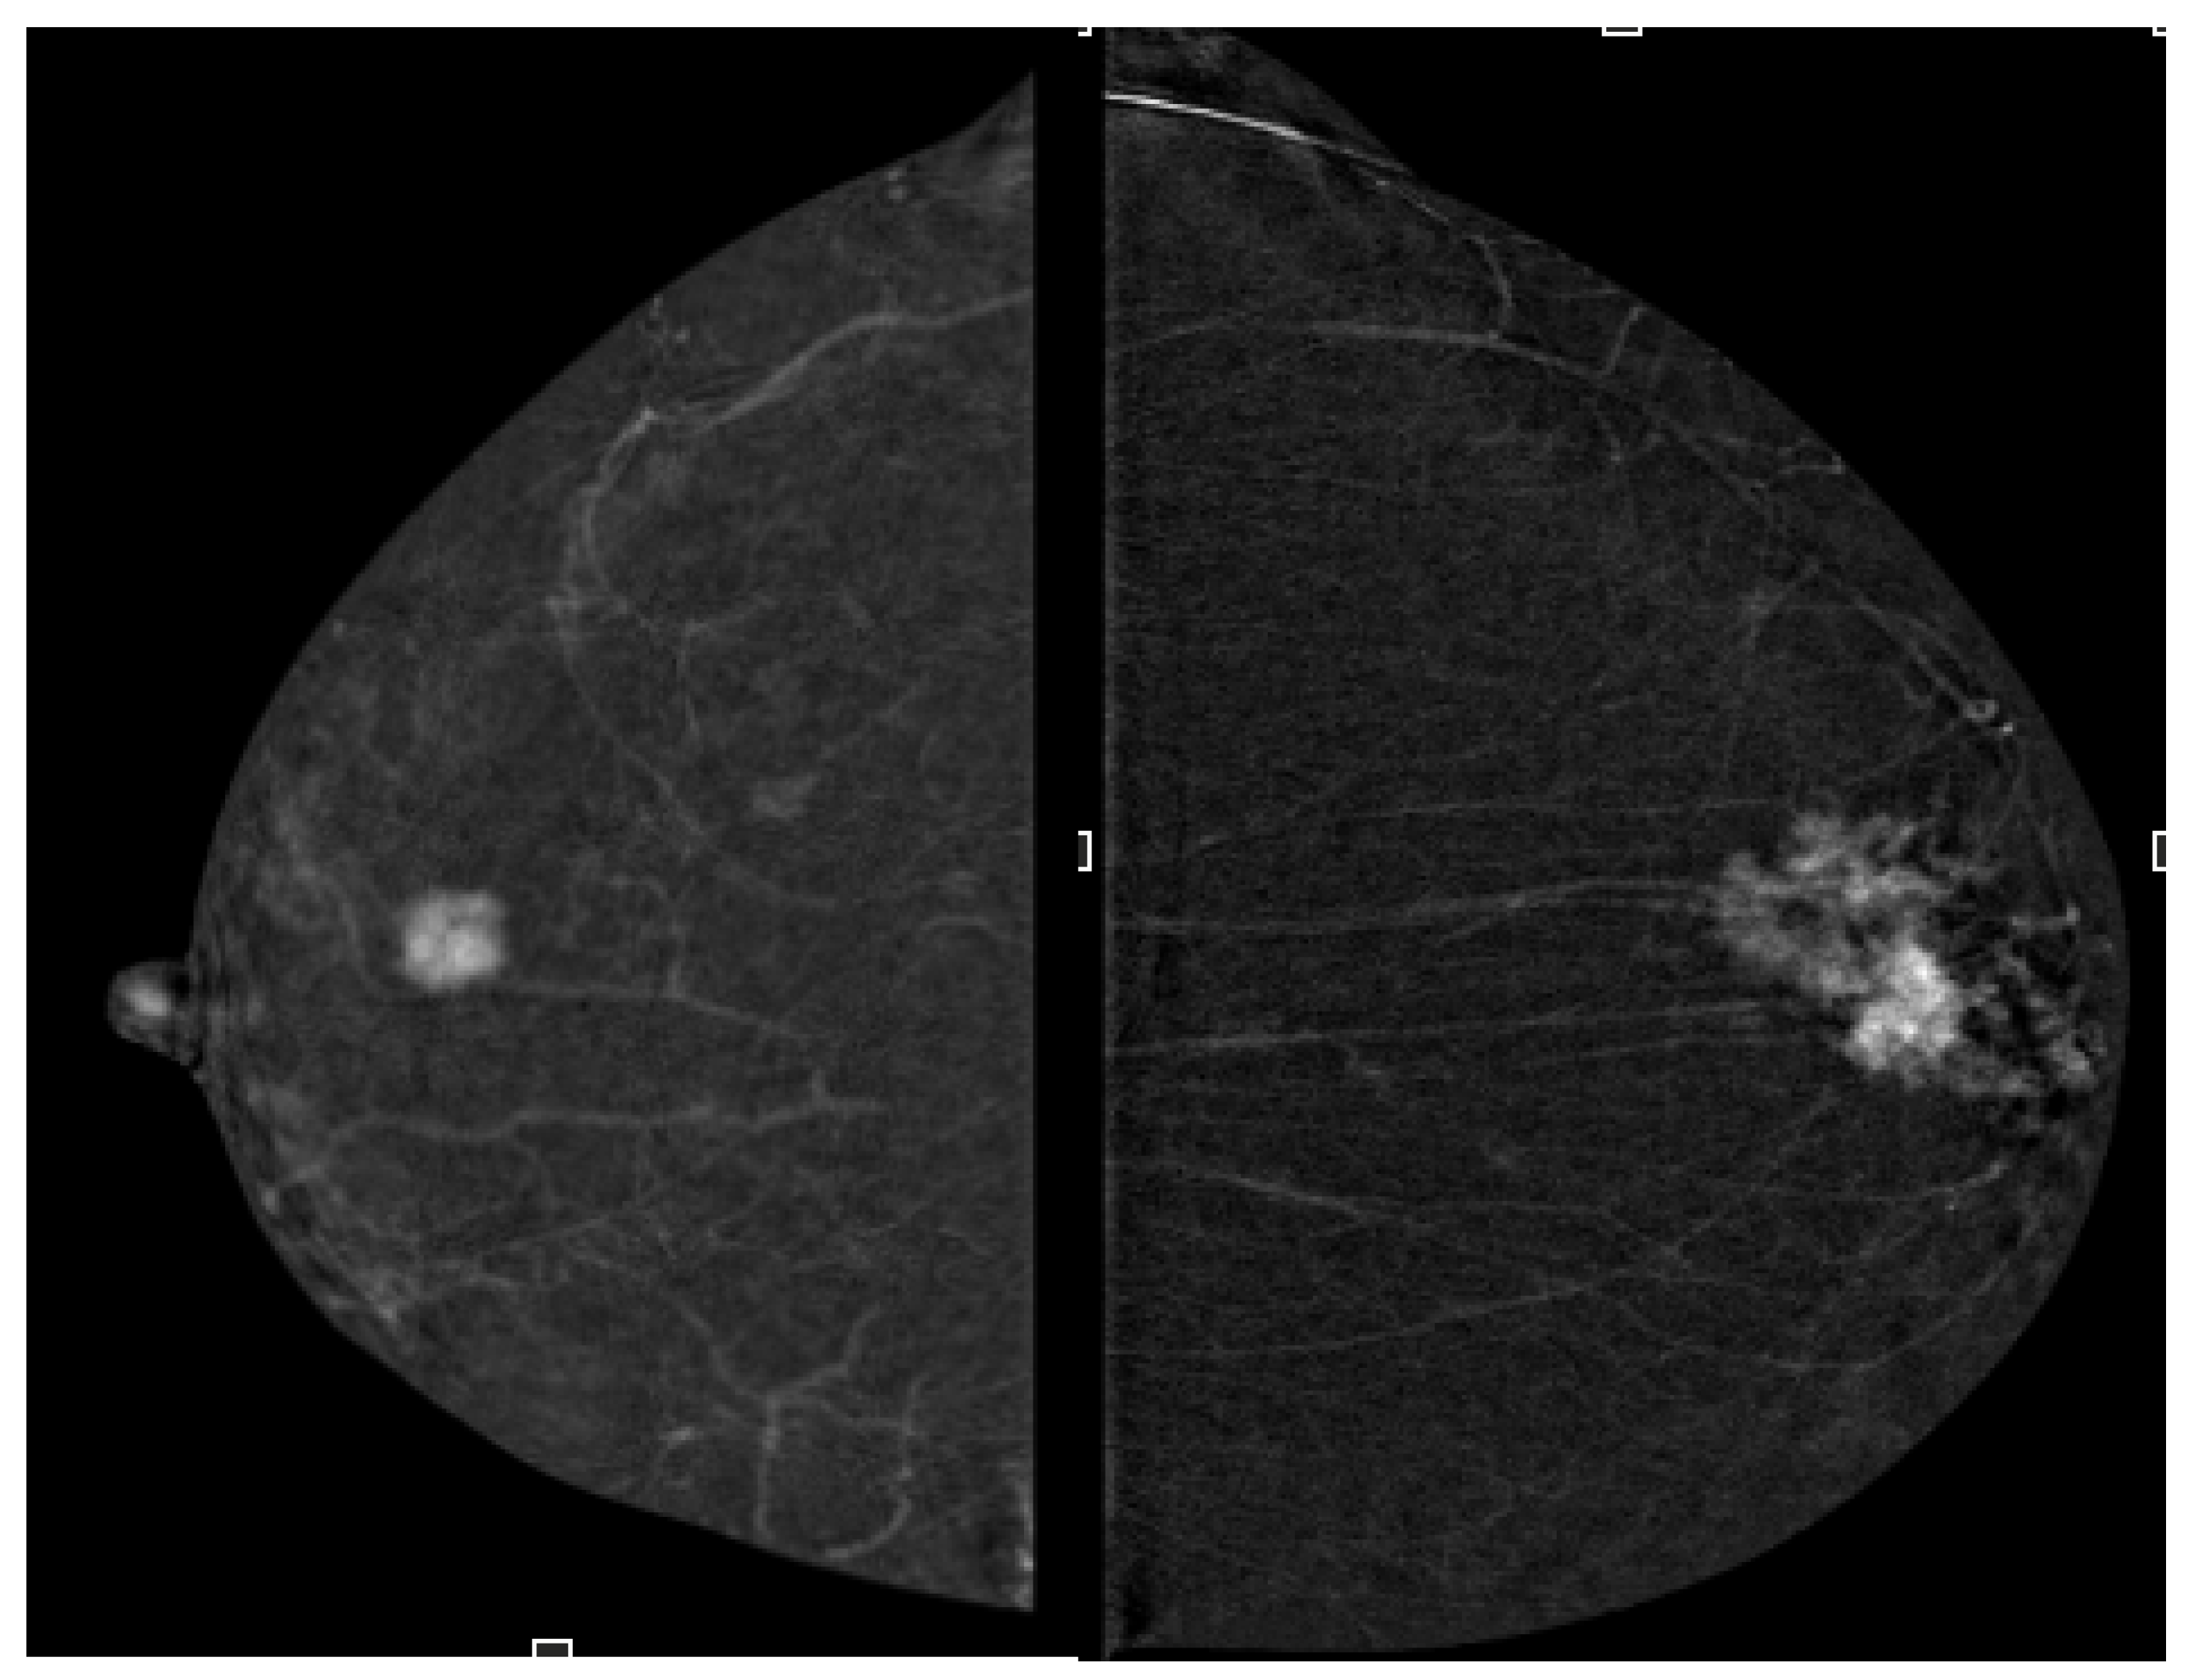

2.4. Image Analysis

- Enhancement intensity: high, moderate, low (visual signal relative to parenchyma),

- Enhancement homogeneity: homogeneous vs. heterogeneous (uniformity of contrast distribution).